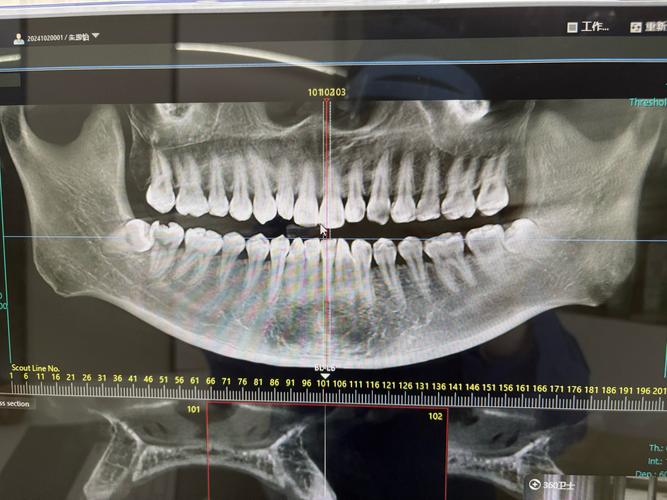

种植牙相当于在牙槽骨中“打桩”,牙槽骨的高度、宽度、密度直接决定种植体能否稳定植入和长期使用,普通X光片(如根尖片、曲面断层片)虽能显示骨大致情况,但存在明显局限性:它是二维重叠影像,无法准确测量骨的垂直高度和水平宽度,尤其对后牙区(如下颌后牙、上颌后牙)的骨量评估误差较大,可能因角度偏差导致实际骨量比预估更少。

而CT(口腔种植常用锥形束CT,简称CBCT)能生成三维立体图像,可精确测量牙槽骨的骨高度(如种植区距离上颌窦底、下颌神经管的距离)、骨宽度(是否足够容纳种植体直径)、骨密度(骨密度过低会影响种植体骨结合),若上颌后牙区牙槽骨高度不足5mm,种植体可能穿入上颌窦,引发感染或种植体失败;若下颌骨宽度不足5mm,植入种植体时可能损伤下牙槽神经,导致下唇麻木,CT能清晰显示这些关键数据,帮助医生判断是否需要植骨、骨增量,或选择更短的种植体,避免盲目手术。